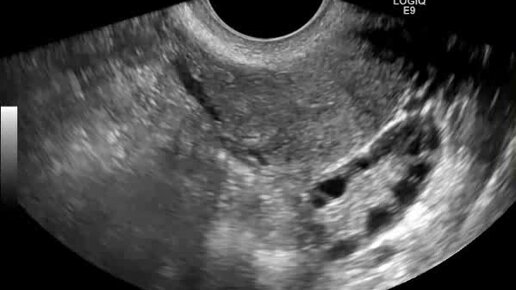

Видео: левый яичник расположен по заднебоковой стенке матки

Ультразвуковые находки от врача УЗД Зорина Я.П.